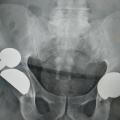

• les interventions prothétiques non conservatrices (fig. 1).

Les causes sont variables : hématome, ­lésion des parties molles, infection débutante, démontage de l’ostéosynthèse, ­luxation ou fracture périprothétique (fig. 4). Un avis chirurgical urgent doit être sollicité, parfois précédé d’un bilan d’imagerie radiologique simple et d’un ­bilan biologique (hémogramme, protéine C réactive [CRP]).

Surveillance et durée de vie d’une prothèse

Une dégradation fonctionnelle tardive peut traduire une évolution de la pathologie initiale ou la dégradation du traitement (descellement de prothèse, arthrose après ligamentoplastie…). Si une prothèse est présente, même en cas de pathologie de voisinage, comme une cruralgie, un bilan radiologique de l’implant doit être effectué.

Les prothèses articulaires doivent être revues à intervalles réguliers car elles peuvent montrer des signes d’usure et/ou un descellement, initialement révélé par des radiographies et conduisant, en l’absence de signes cliniques, à une surveillance plus rapprochée. En cas de signes cliniques et selon l’état général, le changement de prothèse est souvent possible, avec une morbidité actuelle moindre.

La durée de vie d’une prothèse ne peut pas être prédite individuellement. Mais hors complications (infections, fracture…), elle est en moyenne de vingt ans. Cette durée varie en fonction de l’indication initiale, des antécédents locaux et généraux et de l’activité du patient.

La survenue tardive d’une première luxation de prothèse de hanche après un geste banal traduit une usure de la pièce cotyloïdienne, une fracture tardive sur implant céramique ou une altération musculaire des fessiers. Dans ce contexte, une reprise uni- ou bipolaire doit être évoquée, sans attendre une récidive de la luxation.